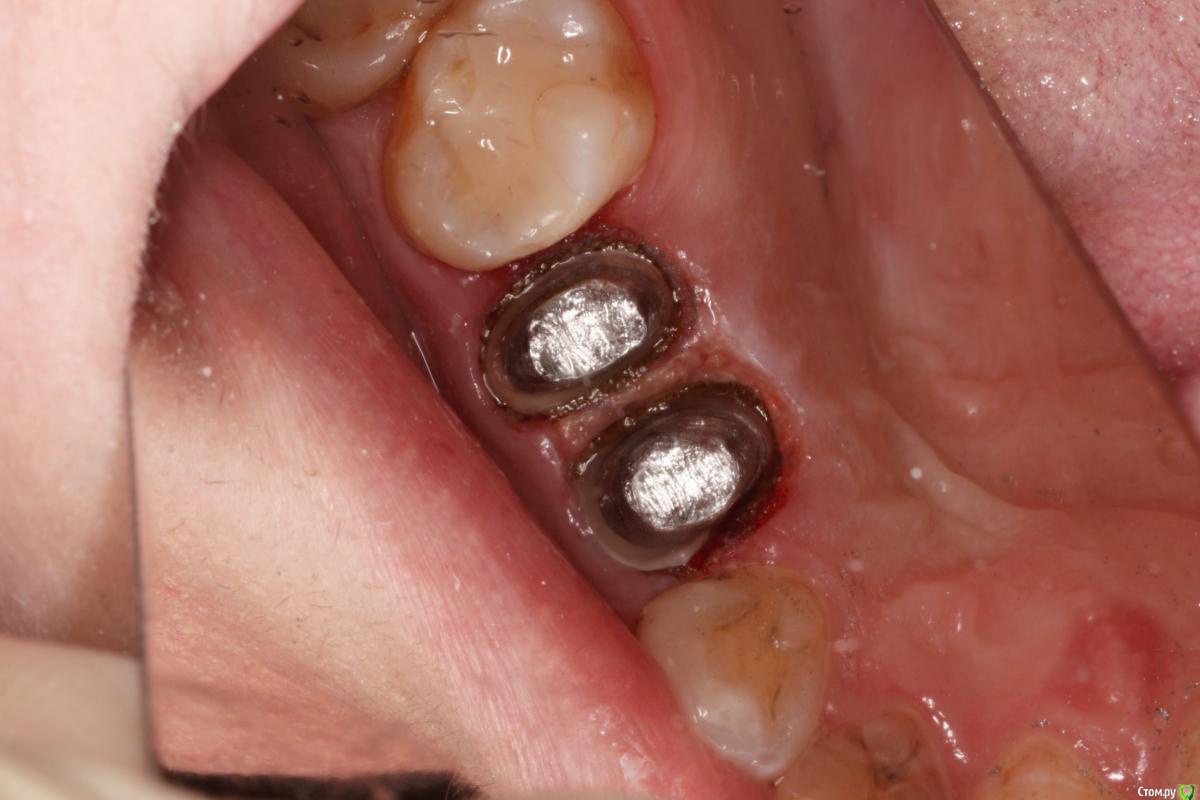

skeettrap Опубликовано 5 июля, 2016 Поделиться Опубликовано 5 июля, 2016 Стандартная ситуация : коллега попросила сделать родственнице (мужа) за неделю - во время краткосрочного визита из Израиля.Исходная ситуация 14,15 сильно разрушены с временными пломбами и наплывшей десной(фото не сделал).На первом этапе сделаны культевые вкладки прямым методом (десну подрезал бором). Постановка вкладок на следующий день, изготовление временных коронок, снятие слепков. Через 2 дня - фиксация. Ссылка на комментарий